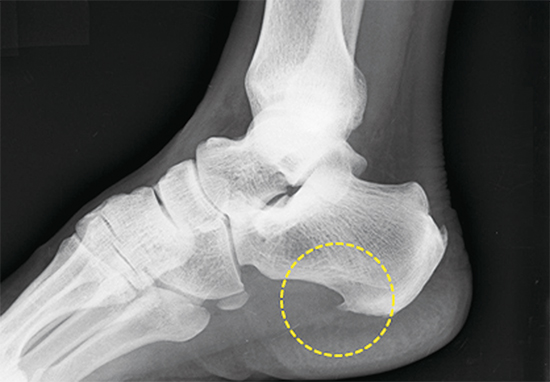

족저 근막은 종골에서 시작하여 발바닥 앞쪽으로 5개의 분지를 내어 발가락 기저부에 부착되는 강인하고 두꺼운 섬유 띠입니다.

이는 발의 아치를 유지하고 체중 부하 상태에서 발을 올리는데 도움을 줍니다. 족저 근막염은 족저 근막에 미세한 손상이 반복해서 발생하여 콜라겐이 변성되고 퇴행성 변화로 통증이 유발되는 질환입니다.

가장 흔하게 나타나는 족부 병변 중 하나로 뒤꿈치의 통증을 일으키는 질환입니다. 장시간 서있거나 과도한 운동 , 몸무게 증가, 하이힐 등 발에 스트레스가 증가하면 더 쉽게 발병합니다.